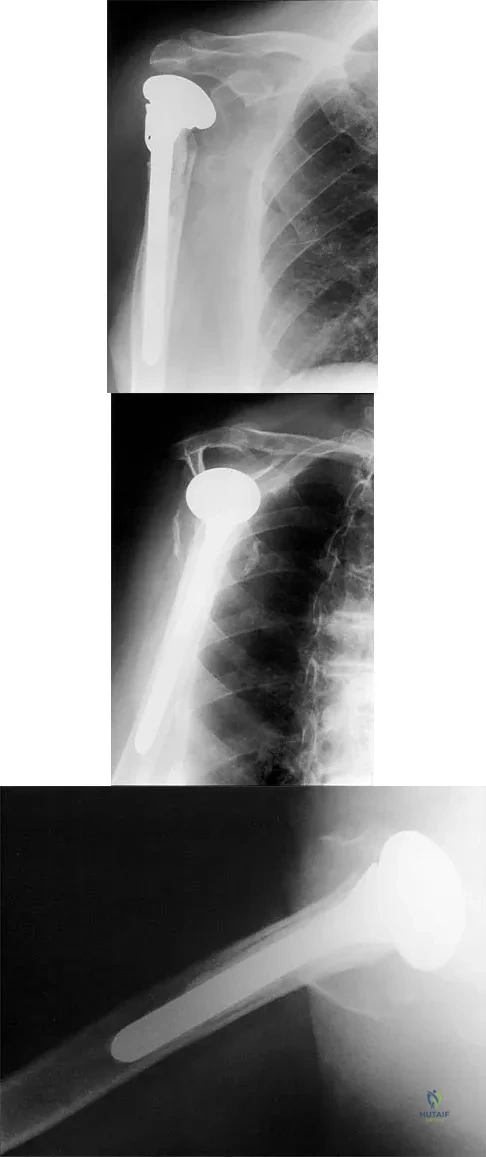

A 68-year-old woman has been progressing slowly after undergoing humeral head replacement for a four-part fracture 3 months ago. She has not regained active elevation, she feels an audible clunk on attempting elevation, and she reports pain and weakness. She used a sling for 2 weeks in the immediate postoperative period. Radiographs are shown in Figure 37a through 37c. Management should consist of